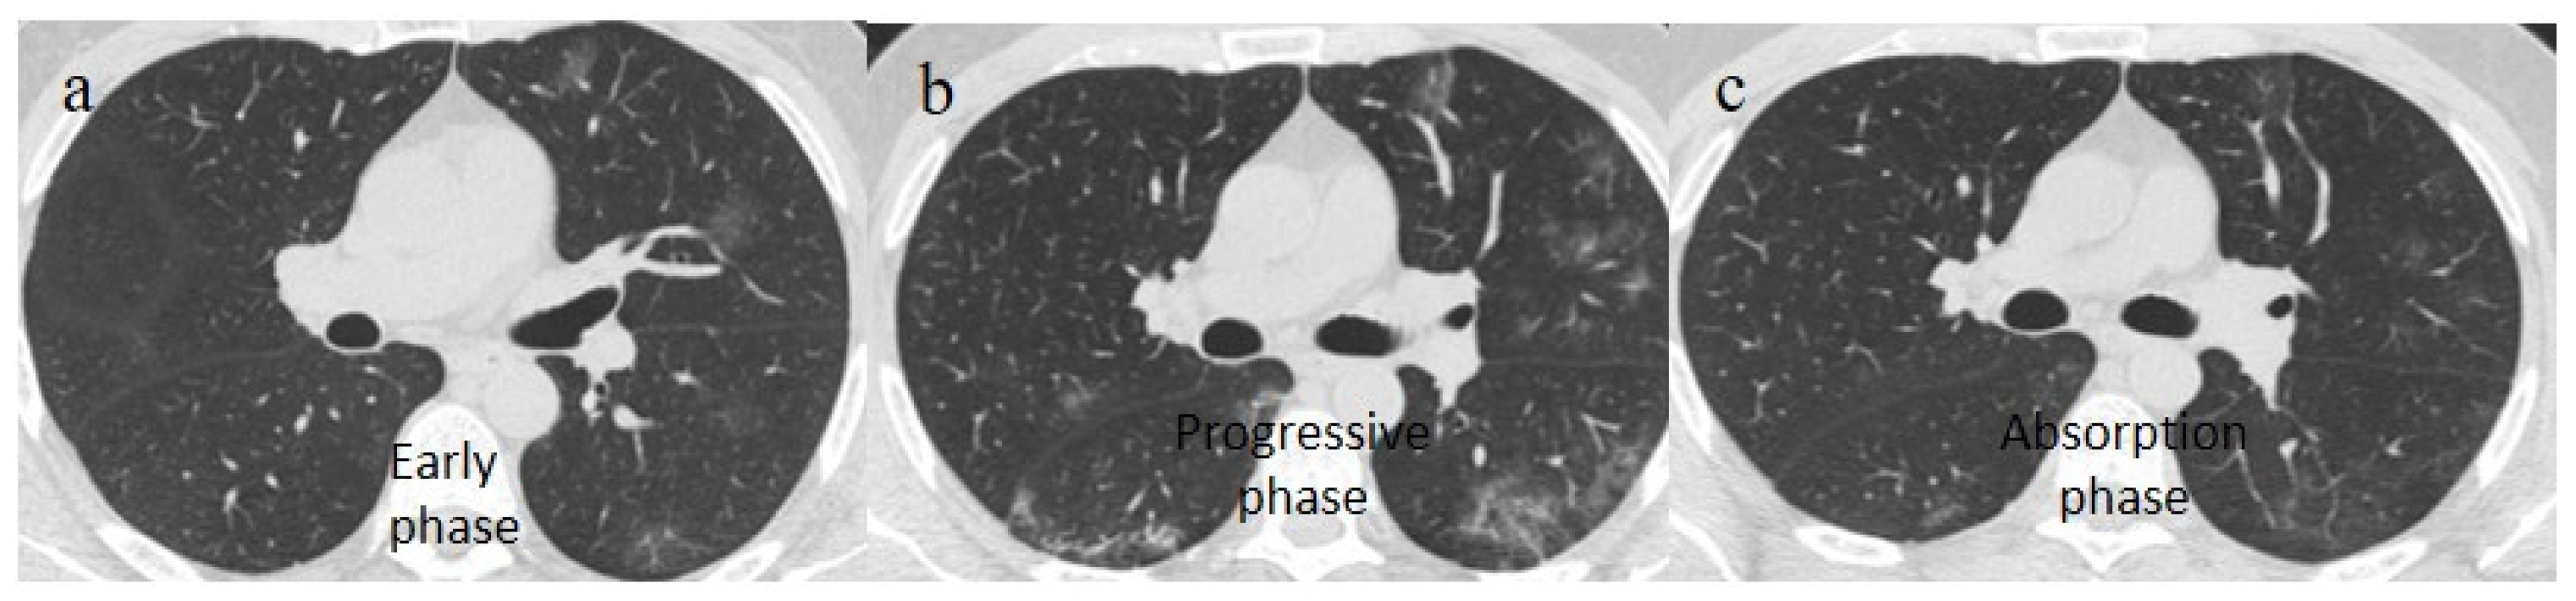

| Typical Appearance | GGOs with a crazy-paving pattern and consolidations in a peripheral and posterior or central-peripheral distribution; multilobar involvement; vascular enlargement, the halo and reversed halo sign; subpleural and parenchymal bands; and architectural distortion. They were predominant since the Delta wave. |

| Typical appearance | From the wild-type to the Delta variant. | Askani et al., 2022 [67] | The Delta variant presented more frequent typical features with more extensive lung involvement than the Omicron variant. The Omicron variant was more frequently associated with the absence of pneumonia. |

| Inui et al., 2021 [68] | Typical findings were characteristic of the wild type to the Delta variant. GGOs with consolidation and repair changes were more frequent in the Delta variant. The Delta variant also showed more rapid pneumonia progression than the wild-type and Alpha variants. | ||

| Lee et al., 2023 [28] | Typical CT patterns were more frequent in the Delta group (76%) than in those with the Omicron variant (42%). | ||

| Yoon et al., 2023 [69] | Only 32% of patients with the Omicron variant presented typical findings, compared with 57% of the Delta variant cases. | ||

| Typical findings of interstitial pneumonia with peripheral or peripheral central distribution from the wild/type variant since Delta variant |

| Absence of pneumonia or atypical findings during the Omicron wave | |||